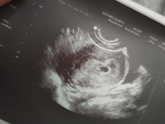

6 сентября 2022 20:35 Первое УЗИ В общем сегодня сходила к гинекологу, посмотрела на «точечку», назначили фолиевую и папаверин свечки, физический и половой покой, так как есть УПБ. Надеюсь что через десять дней на контроле услышу сердечко ❤️.